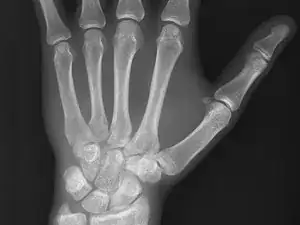

Medical imaging is the process of creating visual representations of the internal structures of the body beneath the skin and bones. These images can then be used for clinical analysis, diagnosis and discovery of abnormalities, and to create plans for medical intervention. Medical imaging uses a variety of technologies based on the area of analysis, including but not limited to “X-ray radiography, magnetic resonance imaging, ultrasound, endoscopy, elastography, tactile imaging, thermography, medical photography, and nuclear medicine functional imaging techniques as positron emission tomography (PET) and single-photon emission computed tomography (SPECT).” (Wikipedia)